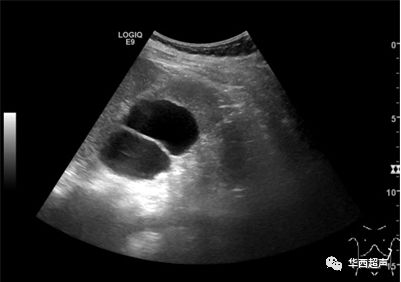

左肾形态失常,大小约13.7x4.2x4.2cm,上肾实质菲薄,上肾集合部最大分离暗区约5.4cm,内未见确切强回声团。下肾实质回声未见异常,集合部未见明显分离暗区及强回声团。右肾、双侧输尿管、膀胱未见异常。

诊断提示:左肾重复肾,上肾重度积水。

病理诊断:肾实质灶区萎缩,结构紊乱;肾盂平滑肌束肥厚及分布异常。病变符合重复肾改变。